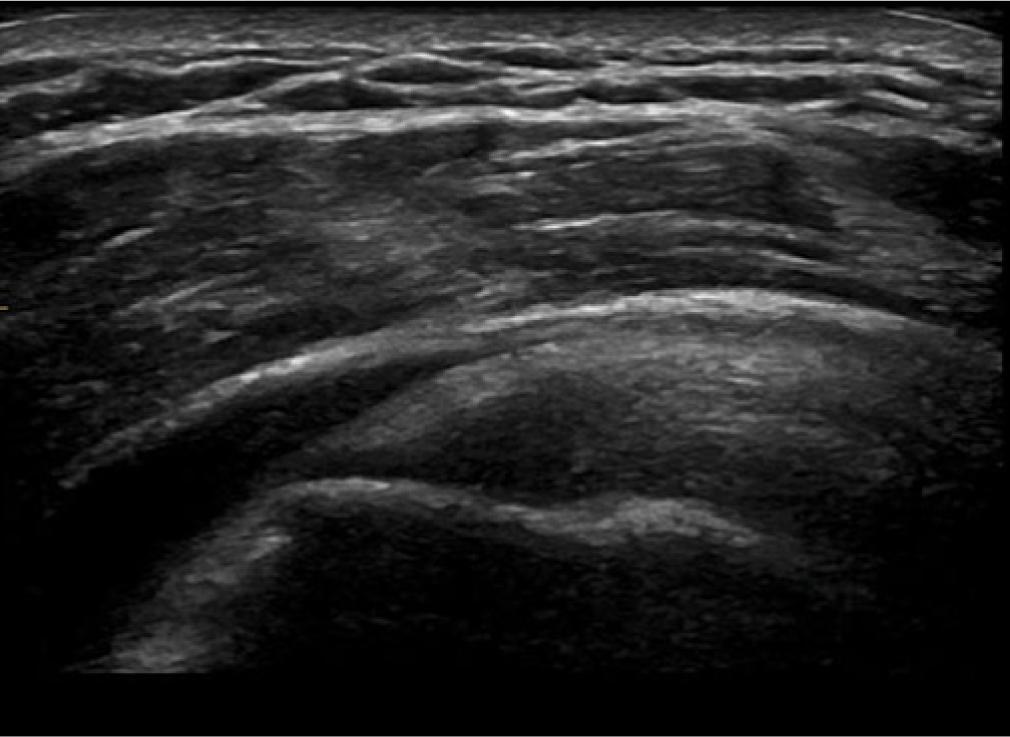

The bursa should be seen as three parallel stripes. The top and bottom should be of high echogenicity compared to the low central stripe (Fig. 1). If the lower stripe is not seen, then this would imply a bursal surface supraspinatus or infraspinatus fraying (Fig. 2). If the stripes are not clear in outline, appearing blurred, then the presence of an adhesive bursitis should be considered (Fig. 3). In a child or young adult, the central stripe may be very thin, and the bursa may appear as one stripe if the resolution of the ultrasound machine is poor.

The 3 distinct stripes of the subdeltoid subacromial bursa are seen here